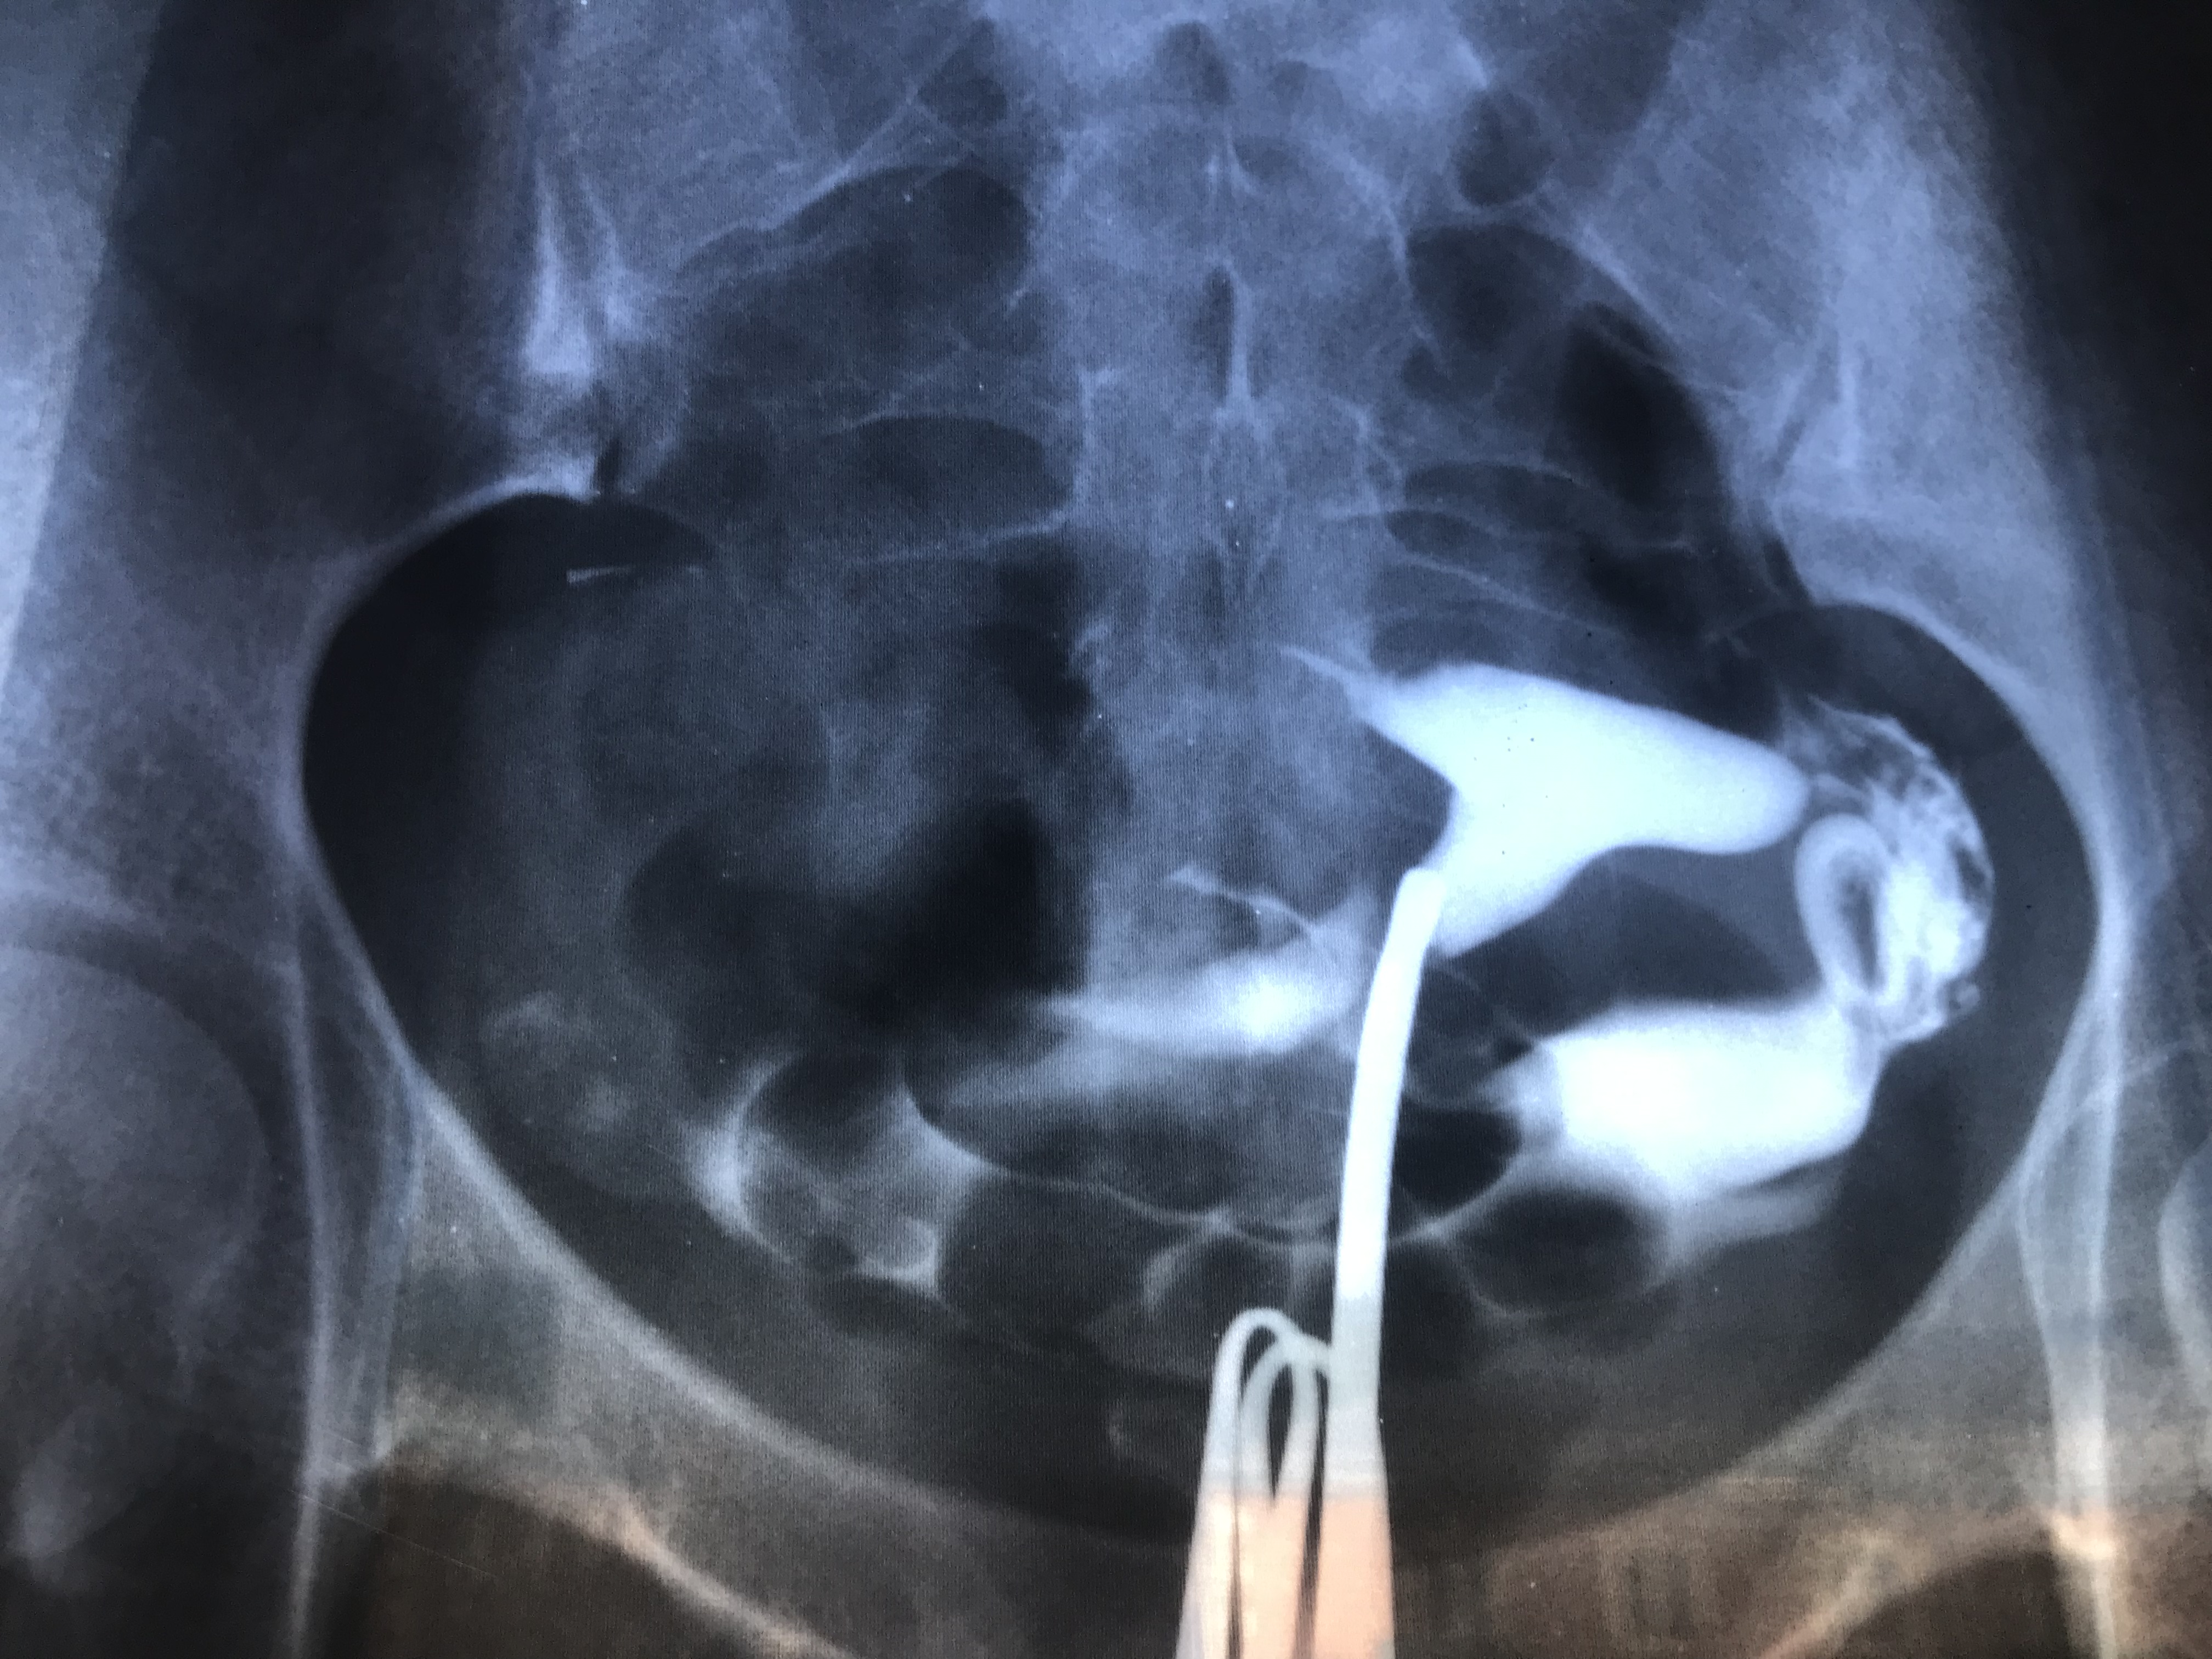

Медицинские снимки: Проходимость маточных труб